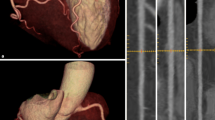

Utilizing the 3D fused images, four out of ten (40%) stenoses ≥ 50% seen at cCTA had CT/SPECT MPI perfusion defects in their corresponding myocardial territory. Six perfusion abnormalities on fused images had no correlate at cCTA. In one patient (Fig. 4) a small apical perfusion defect was not appreciated by the observers, both on routine clinical SPECT MPI and on the isolated SPECT component of the CT/SPECT investigational system. cCTA in this patient showed significant LAD stenosis which was later confirmed by catheter angiography. On fused CT/SPECT display (Fig. 4), the perfusion defect can be more clearly visualized.

Routine clinical SPECT MPI (a) and CT/SPECT (b) in a 55-year-old man (Table 2, patient 1) with typical exertional angina and cardiovascular risk factors clinically referred for myocardial perfusion imaging. The routine clinical SPECT MPI (a) was interpreted as normal, without perfusion defects by the observers. cCTA (b) displayed as transverse section (right upper panel) and curved multiplanar reformat (right middle panel) shows high degree stenosis of the mid LAD caused by mixed calcified and noncalcified plaque (arrows), subsequently confirmed at invasive catheter angiography (right lower panel) and treated despite rather small perfusion defect but typical angina by stent placement. In retrospect the stress MPI study using the CT/SPECT system (left lower panel in b) shows a small apical area with reduced perfusion (arrows) which was initially not appreciated by the observers. Also shown are the attenuation-corrected (upper row) and uncorrected (lower row) studies in short, long horizontal, and long vertical axes. On fused CT/SPECT display (left upper panel in b), the perfusion defect can be more clearly visualized. Upper middle image panel shows the overlay of myocardial outlines generated at MPI (color) and at CT (grayscale) as a first step of the fusion process used for quality control